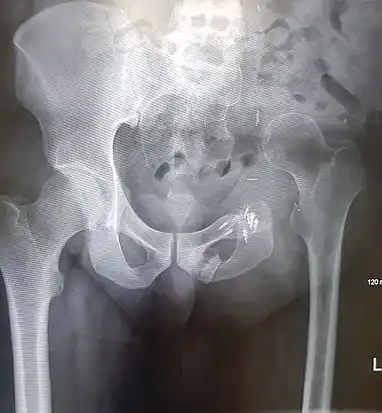

An x-ray of a limb-sparing hemipelvectomy on the left side of a male pelvis taken one month after surgery.

An x-ray of a limb-sparing hemipelvectomy on the left side of a male pelvis taken one month after surgery. An x-ray of the same pelvis taken eighteen months after surgery highlighting the femur migration to its final resting place.

An x-ray of the same pelvis taken eighteen months after surgery highlighting the femur migration to its final resting place.